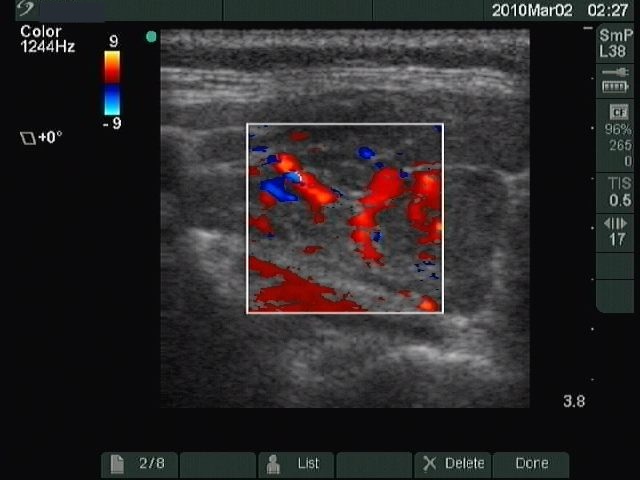

Ultrasonography: revealed a hypoechogenic thyroid with a large echonormal nodule in the left lobe.